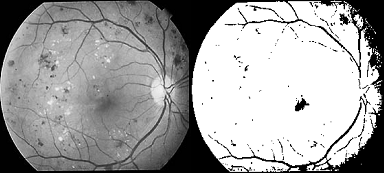

A number of methods for optic disc detection and blood vessels detection have been published. Osareh et al. [6] located the optic disc center by means of template matching and extracted its boundary using a snake initialized on a morphologically enhanced region of the optic disc. Lowell et al. [7] also localized the OD by means of template matching as well as also selected a deformable contour model for its segmentation. Another deformable model-based approach was presented in [8]. Another template-matching approach for OD segmentation is the Hausdorff-based template matching presented by Lalonde et al. [9]. Initially, they determined a set of OD candidate regions by means of multi resolution processing through pyramidal decomposition. For each OD region candidate, they calculated a simple confidence value representing the ratio between the mean intensity inside the candidate region and inside its neighborhood. As final step, using the Hausdorff distance between the edge map regions and circular templates with different radii, they decided the OD among all the candidates. There are some methods for blood vessels detection in retinal fundus images such as region growing technique [10] All possible thresholds are evaluated in this way, and the one that maximizes ? is chosen as the optimal threshold. The closing (morphology) operator is useful in detection of vessels. While using closing operator it is important to select structuring element. The closing is a dilation followed by erosion that joins the very close objects together. Then, the result image is binaries by thresholding using Otsu algorithm [16]. The result image is shown in Fig. 6 (b).The filling operator is applied to fill the holes in the image and the result image is shown in Fig. 6 (c). The result image is reconstructed by using the morphology reconstruction and is shown in Fig. 6 (d). To detect the optic disc region, the Otsu algorithm is applied on the difference between the original image and the reconstructed image. The optic disc detected area is shown in Fig. 6 (e). The results of the optic disc detection are shown in Fig. 6

![Fig. 5 : (b) Result of averaging filter VII. Result & Discussion Otsu's method is used to detect damaged optic disk & damaged nerve fibers. For which 1) we compute a mean value of colors with maximum intensity by applying a global threshold to convert an intensity image to a binary image. By normalized intensity value that lies in the range [0, 1]. 2) We have removed a Noise of grayscale image & then applied adaptive wiener filtering & by median filter; by estimating the local mean and variance around each pixel. Thus as shown in figure (1 & 2) only selected damage nerve fibers & optic disk is observed.](https://medicalresearchjournal.org/index.php/GJMR/article/download/100601/version/100601/5-Optic-Disc-and-Blood-Vessels_html/10168/image-8.png)